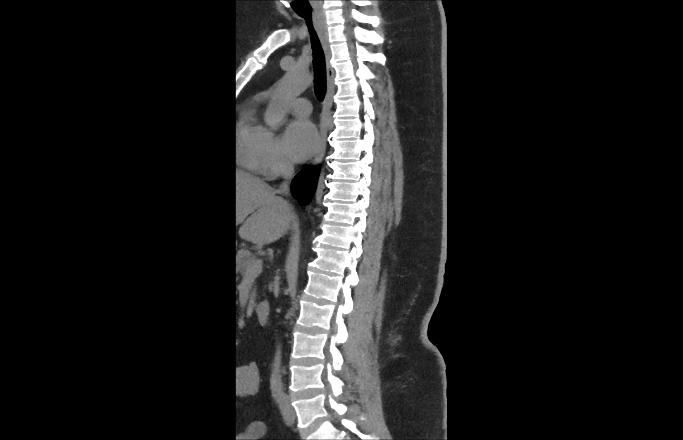

I’ve been diagnosed with Diffuse Idiopathic Skeletal Hyperostosis (DISH) and degenerative disc disease — both cause my spinal bones to stiffen and press on nerves. The pain runs across my lower back, hips, and legs, and sometimes even causes numbness around my lower back and thighs. I’ve tried to keep pushing through, but lately, even sleeping or sitting too long hurts.